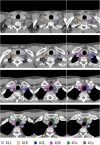

The purpose of this study was to develop a consensus-based computed tomographic (CT) atlas that defines lymph node stations in radiotherapy for lung cancer based on the lymph node map of the International Association for the Study of Lung Cancer (IASLC). A project group in the Japanese Radiation Oncology Study Group (JROSG) initially prepared a draft of the atlas in which lymph node Stations 1-11 were illustrated on axial CT images. Subsequently, a joint committee of the Japan Lung Cancer Society (JLCS) and the Japanese Society for Radiation Oncology (JASTRO) was formulated to revise this draft. The committee consisted of four radiation oncologists, four thoracic surgeons and three thoracic radiologists. The draft prepared by the JROSG project group was intensively reviewed and discussed at four meetings of the committee over several months. Finally, we proposed definitions for the regional lymph node stations and the consensus-based CT atlas. This atlas was approved by the Board of Directors of JLCS and JASTRO. This resulted in the first official CT atlas for defining regional lymph node stations in radiotherapy for lung cancer authorized by the JLCS and JASTRO. In conclusion, the JLCS-JASTRO consensus-based CT atlas, which conforms to the IASLC lymph node map, was established.